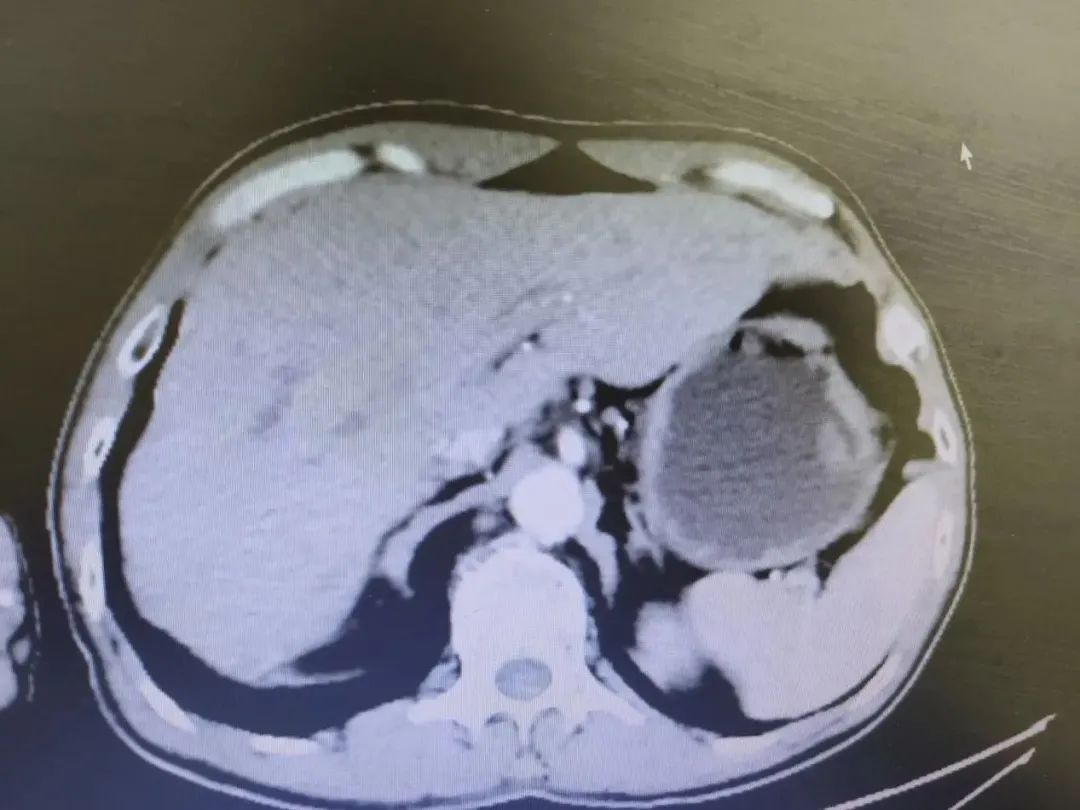

经过化疗科科室讨论后为患者制定规范的个体化治疗方案,于2022年2月11日至2022年6月28日开始行免疫检查点*制剂抑**联合全身姑息性化疗7周期,患者全程化疗及免疫副反应轻,依存性好。于2022年3月28日两周期化疗后我院全面复查腹部增强CT提示肝内多发转移(2.8x1.9cm),较治疗前(5.2x6.5cm)明显缩小。评估疗效:PR。原方案化疗4周期后复查肝脏转移灶在进行性减少和缩小,病灶持续缓解。2022年5月13日我院无痛胃镜及活检:(胃体)慢性萎缩性胃炎,萎缩(中度),炎症(中度,伴急性活动性炎)。此次查胃镜活检提示未见肿瘤性病灶,继续行原方案治疗,第4、6周期原方案治疗(4周期后肝转移灶较大者大小约2.4x1.4cm,6周期后肝转移灶较大者大小约2.3×1.5cm)。

我院化疗前影像(2022年2月10日)

我院2周期化疗后影像(2022年3月28日)